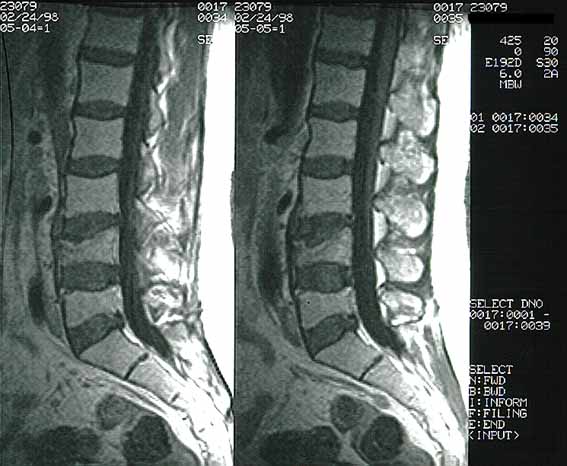

Figura 4. RNM con gadolinio. Fractura por compresión de cuerpos vertebrales L4-L5